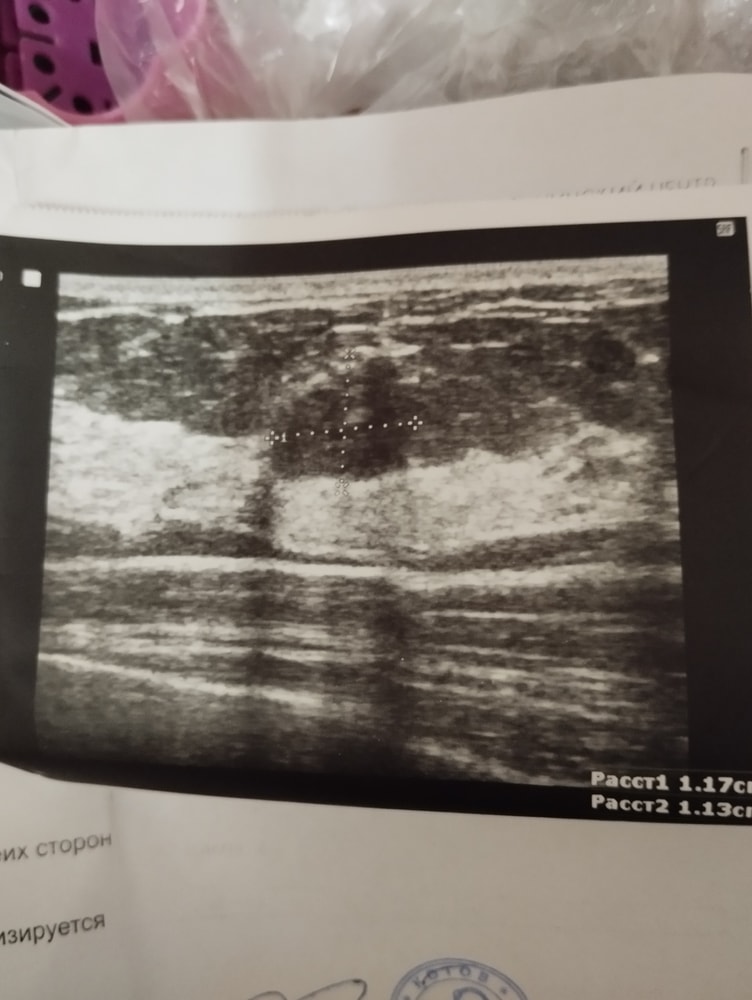

Сходила на узи, вроде бы по результатам все хорошо, но описание не вяжется с снимком. Написано, что контуры ровные, структура однородная, но по снимку этого не скажешь. Написано, что фиброаденома, но образование имеет ширину почти равную высоте и потому на "добро" не очень похоже. Конечно, я уже записалась переделать узи и к онкологу. Запись только на 5 апреля, очень переживаю((

Ольга , спасибо вам за ответ. Знаю, что частая штука. Сомневаюсь, что в данном случае это фиброаденома. По снимку не очень похоже